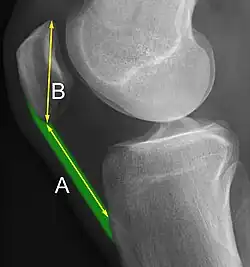

A patella alta is a high-riding (superiorly aligned) patella. An attenuated patella alta is an unusually small patella that develops out of and above the joint.

A patella baja is a low-riding patella. A long-standing patella baja may result in extensor dysfunction.[6]

The Insall-Salvati ratio helps to indicate patella baja on lateral X-rays, and is calculated as the patellar tendon length divided by the patellar bone length. An Insall-Salvati ratio of < 0.8 indicates patella baja.[7]